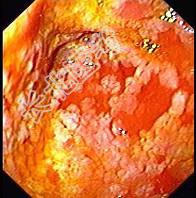

- 单项选择题男性,67岁, 反复上腹饱胀不适2年,以餐后为甚, 伴反酸、嗳气、食欲不振、恶心、呕吐等。胃镜检查胃窦粘膜见散在灰白色斑块,如图: 该病人最可能的诊断是 ( )

A、胃黄斑瘤

B、慢性浅表性胃炎

C、慢性萎缩性胃炎伴肠上皮化生

D、胃泌素瘤

E、消化性溃疡